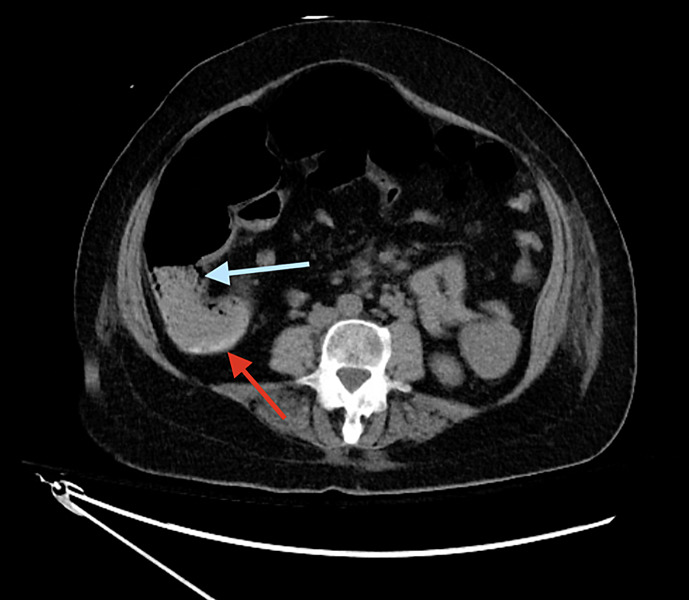

Case presentation: This report highlights a case of rIVCF used in the management of recurrent VTEs in a patient hospitalized for persistent gastrointestinal bleeding.